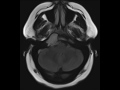

Chondrosarcoma, Skull Base

This is a 56-year-old female who presented for dysphagia, diplopia, and episodic tinnitus. There is a T2-hyperintense mass centered within the right petroclival region, and involving the right hypoglossal canal, right jugular foramen, and extends to involve meckel’s cave on the right. There is minimal extension to the posterior aspect of the cavernous sinus on the right. The lesion is T1-hyperintense and avidly enhances. There are no suspicious regions of diffusion restriction. Skull base chondrosarcoma are typically off-midline in location, centered on the petro-occipital fissure. Chondroid matrix calcification is present in 50% of cases. The lesion will usually demonstrate a sharp, narrow, nonsclerotic transition zone on CT, as this lesion did.